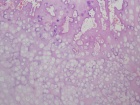

Patient is a 34 y/o female who presents after a hysterosalpingogram revealed a R. femoral lesion

Patient does state a hx. of mild activity related R. hip pain; PMH: unremarkable

PE: no palpable mass or TTP over R. prox. thigh; full PROM hip w/ no tenderness; NVI

Zoom image: Cell stain Cell stain.